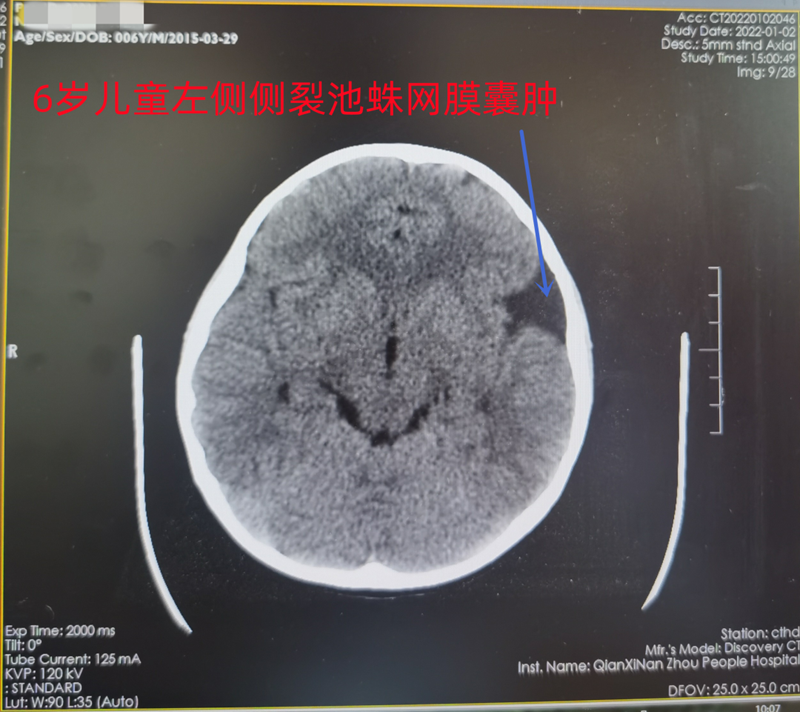

多数蛛网膜囊肿为颅脑损伤或体检时做头颅CT、磁共振而发现,囊肿好发与蛛网膜池相关的部位,如颞部外侧裂、枕大池、小脑桥脑角、鞍上池、脑室内等。